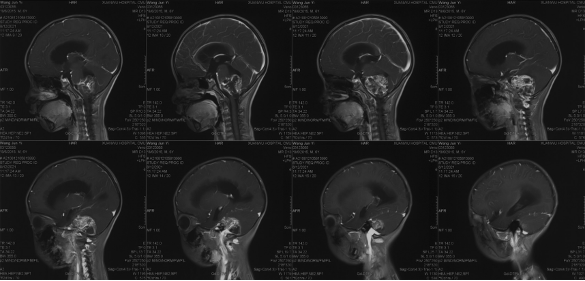

Pre-operative imaging

Preoperative imaging MRI-T2

Preoperative imaging MRI-T1

Preoperative enhanced MRI